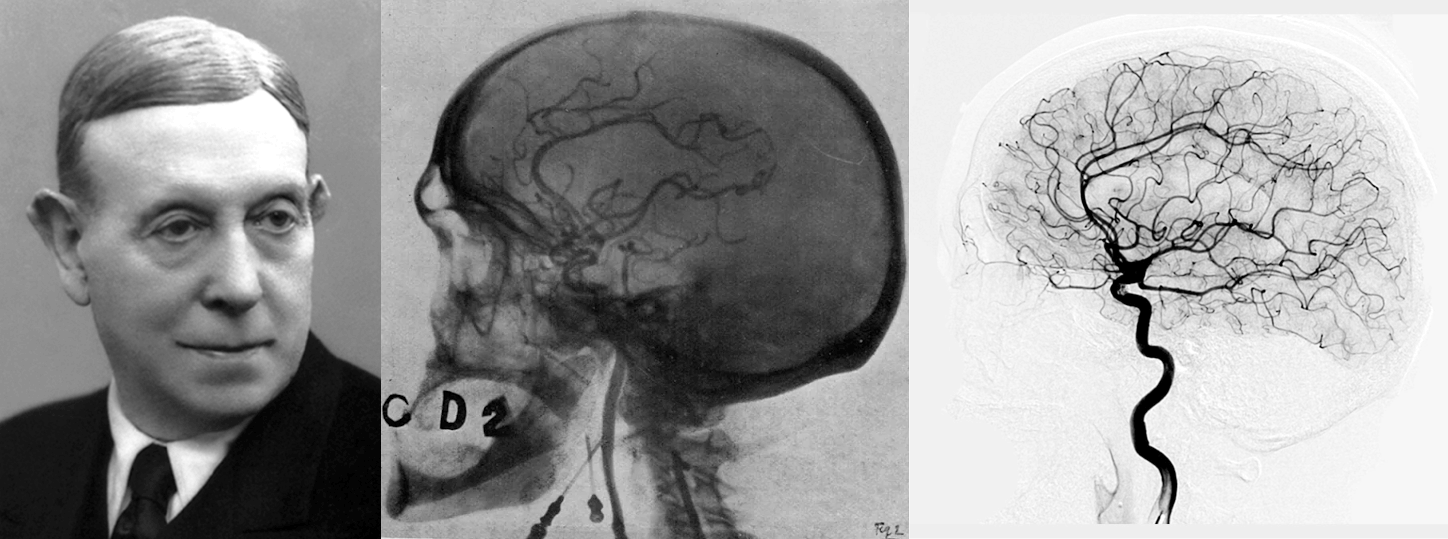

Первые атаки рентгеновскими лучами и ультразвуком отражены черепом

В 1927 году португальский невролог Антониу Эгаш Мониш предложил вводить йодсодержащее рентгеноконтрастное вещество в мозговые сосуды и разработал метод церебральной ангиографии, который до сих пор активно используют сосудистые нейрохирурги (рис. 17В) [69]. Однако Нобелевскую премию Мониш получил не за этот метод, а за разработку лоботомии — запрещенного в настоящий момент метода отсечения трактов лобных долей от остальных частей мозга у душевнобольных пациентов [70], о котором мы еще поговорим в следующей главе.

- Церебральная ангиография —

- рентгенологический метод визуализации просвета сосудов головного мозга высокого разрешения путем введения в артерии контрастного вещества (йодсодержащего препарата). Почитайте также о создателе метода и его противоположных по пользе изобретениях: «Эгаш Мониш: премия за убийство Макмерфи» [70].